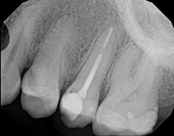

Non-surgical root canal treatment:

Before

After

6-month follow-upThe patient presented with mild pain, a cavity, and a broken filling was evident. After performing diagnostic testing, the diagnosis was: irreversible pulpitis, symptomatic periradicular periodontitis. Root canal therapy was done and the tooth healed well and is still functioning.